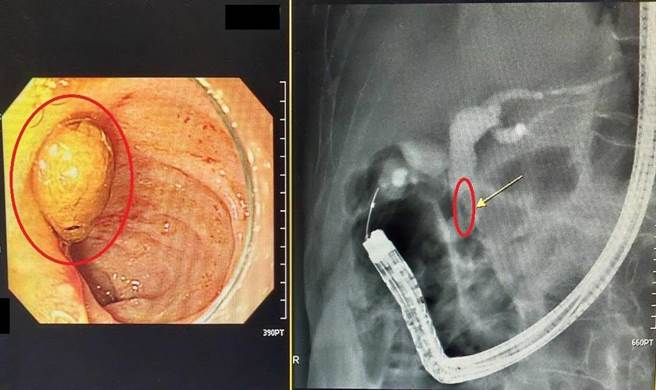

大千醫院指出,陳姓老翁年輕時曾接受過部分胃切除及胃-空腸吻合手術,半年前因胸痛、食慾不佳就醫檢查,發現有總膽管結石,並經由外科手術順利取石。近日,陳姓老翁再因出現黃疸症狀而就醫,檢查發現其總膽管又有一顆結石!考量陳爺爺年紀大,若再次以外科手術取石,風險較高且住院天數較長,與病人及家屬討論後,決定接受內視鏡逆行性膽胰管造影術將石頭取出。

林德福解釋,過去膽管結石多以外科手術為主,現行則多採用內視鏡逆行性膽胰管造影術來診斷及治療,優點是可免於開刀並縮短恢復時間。但是曾經接受過胃手術的病人一旦發生膽管結石,其治療方式相對複雜許多,併發症的風險也較高,因此術前務必經醫師評估並討論後,再依病況安排適合的治療方式,才能提高治療成功率。